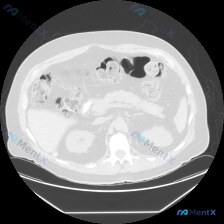

看到一个上腹部CT病例,整理了一下思路,和大家讨论讨论! 病例信息: 影像学检查:上腹部CT(软组织窗,横断面) 观察层面:上腹部胰腺区域 CT表现(关键阳性/阴性信息): 1. 胰腺体尾部及部分头部轮廓可见,周围脂肪间隙弥漫性密度增高,呈毛玻璃样改变,脂肪间隙模糊 2. 双侧肾脏形态及密度未见明显...